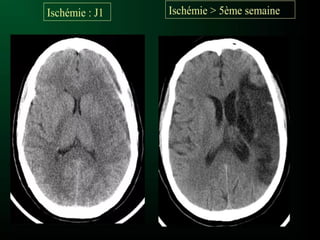

PHASE TARDIVE

SIGNES DIRECT

Sur la TDM on voit une HYPODENSITE

AVC ISCHÉMIQUE PHASE TARDIVE SIGNESDIRECT Sur la TDM on voit une HYPODENSITE intéressant le territoire artérielle atteint